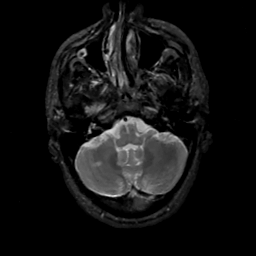

MR Study #14, June 2, 1991 -- Slice #10

[Home][Help][Clinical][Tour 1][Tour 2] Slice 10